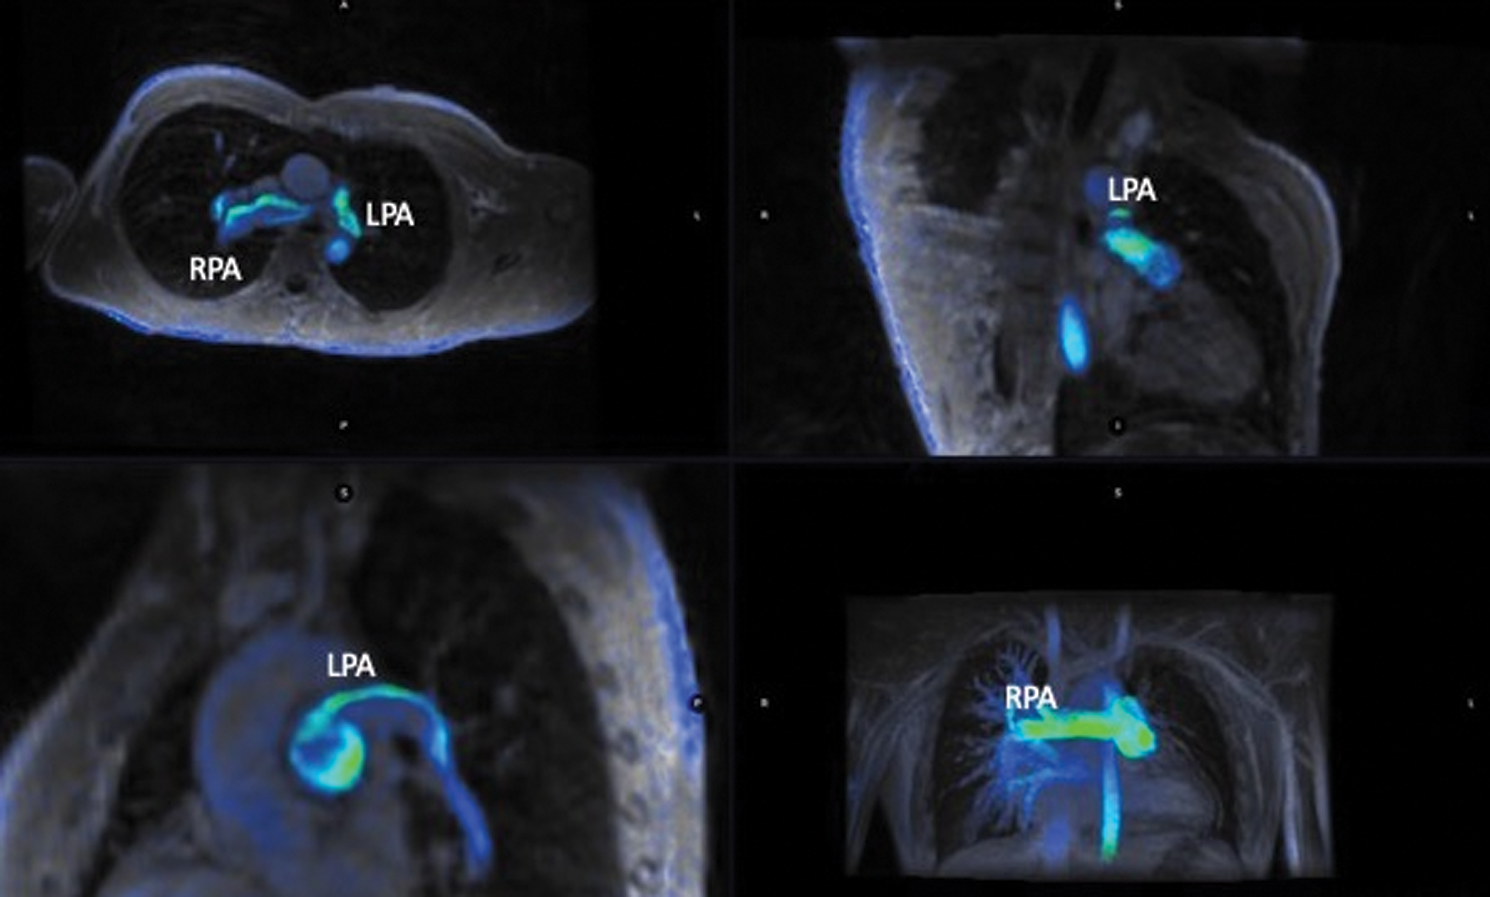

4D flow quantifications were assessed using cloud-based image reconstruction after data correction (Fig. 2, supplementary Video 1).

Figure 2: Multiplanar view of 4D flow acquisition in a patient with left lung hypoperfusion. RPA: Right pulmonary artery; LPA: Left pulmonary artery